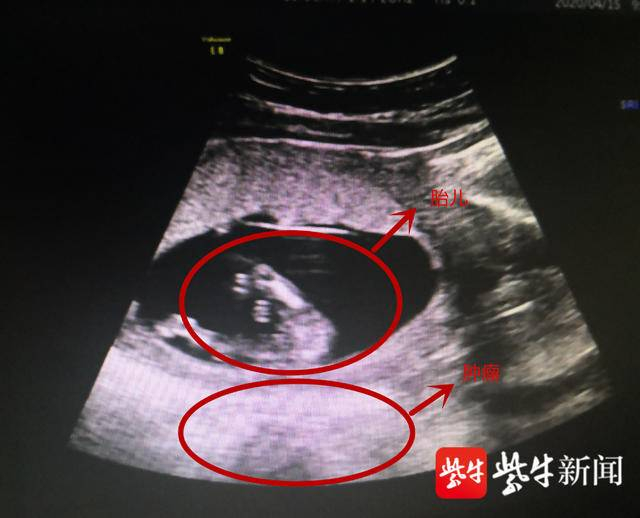

胎儿生命在腹中受直径约10厘米的肌瘤威胁。(院方供图)

在淮安市妇幼保健院,医生再次为赵女士做了全面检查,发现这个肿瘤位于子宫后方,而且和子宫紧密贴合,如果不及时手术摘除,到了孕晚期会发生危险。据淮安市妇幼保健院妇科主任医师冒福云介绍,孕妇孕晚期子宫越来越大,胎儿也会活动,有可能压破肿瘤,引起肿瘤的扭转,一旦肿瘤破裂就会出现腹膜的刺激症状,腹腔的内出血,甚至出现感染、休克,严重会引发流产甚至是胎死宫内的后果。

尽管做了周全的术前分析,但是术中医生发现实际情况要比预判的还要复杂,稍有闪失孩子就可能保不住了。“孕妇怀孕接近14周,子宫比较大,血运丰富。而且这个肿瘤位于子宫的后方,紧贴着子宫,我们几乎没有什么操作空间,要摘除肿瘤就必须移动子宫,移动的过程中可能会刺激子宫引发宫缩造成流产,所以我们就尽量保护周围组织采用一个小切口把肿瘤里面的液体吸出来,减少肿瘤的体积,慢慢游离出来,这样保护了子宫也保护了胎儿。”冒福云告诉记者,整个手术过程有惊无险,医生精准、轻柔的操作保证了手术的顺利,最终病理结果显示这是一个良性的卵巢畸胎瘤,目前胎儿和产妇情况良好。